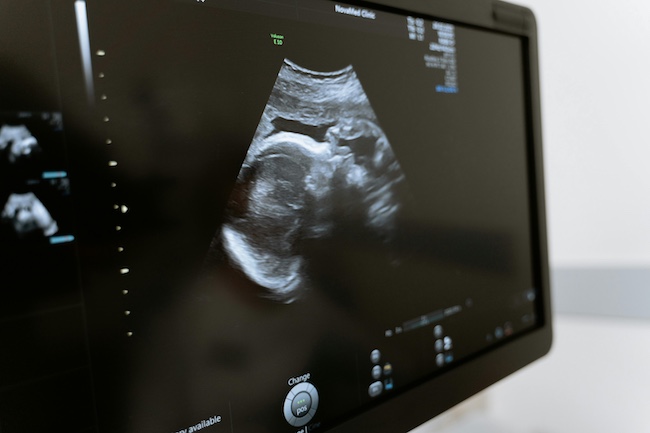

Annotation d'échographies

Annotation de haute précision pour l'échographie abdominale, cardiaque, vasculaire, obstétricale et musculosquelettique.

L'imagerie par ultrasons présente des défis uniques pour le développement de l'IA en raison du mouvement, des angles de sonde variables, des différences techniques entre les opérateurs et des fluctuations de contraste. Une annotation de haute qualité est essentielle pour les modèles qui doivent interpréter l'anatomie dynamique, les limites structurelles, les mouvements physiologiques et les flux de travail cliniques. DataVLab fournit des services d'annotation échographique aux équipes d'IA médicale, aux groupes de recherche et aux entreprises de technologies de la santé qui ont besoin d'un étiquetage structuré selon diverses modalités d'échographie.

Les annotateurs suivent des directives détaillées qui reflètent les conventions anatomiques, l'orientation de la sonde et les exigences spécifiques à la tâche. Nous prenons en charge les échographies abdominales, pelviennes, cardiaques, vasculaires, obstétricales, musculosquelettiques et procédurales. Les tâches d'annotation incluent les masques de segmentation, les polygones, les cadres de délimitation, les repères anatomiques, le suivi des mouvements, la classification des régions et l'étiquetage temporel entre les séquences.

Annotation échographique obstétricale

Étiquetage des points de repère et des régions sur les vues du fœtus

Nous annotons les mesures foetales, les régions anatomiques et les structures pertinentes pour les flux de travail obstétricaux et l'évaluation biométrique.